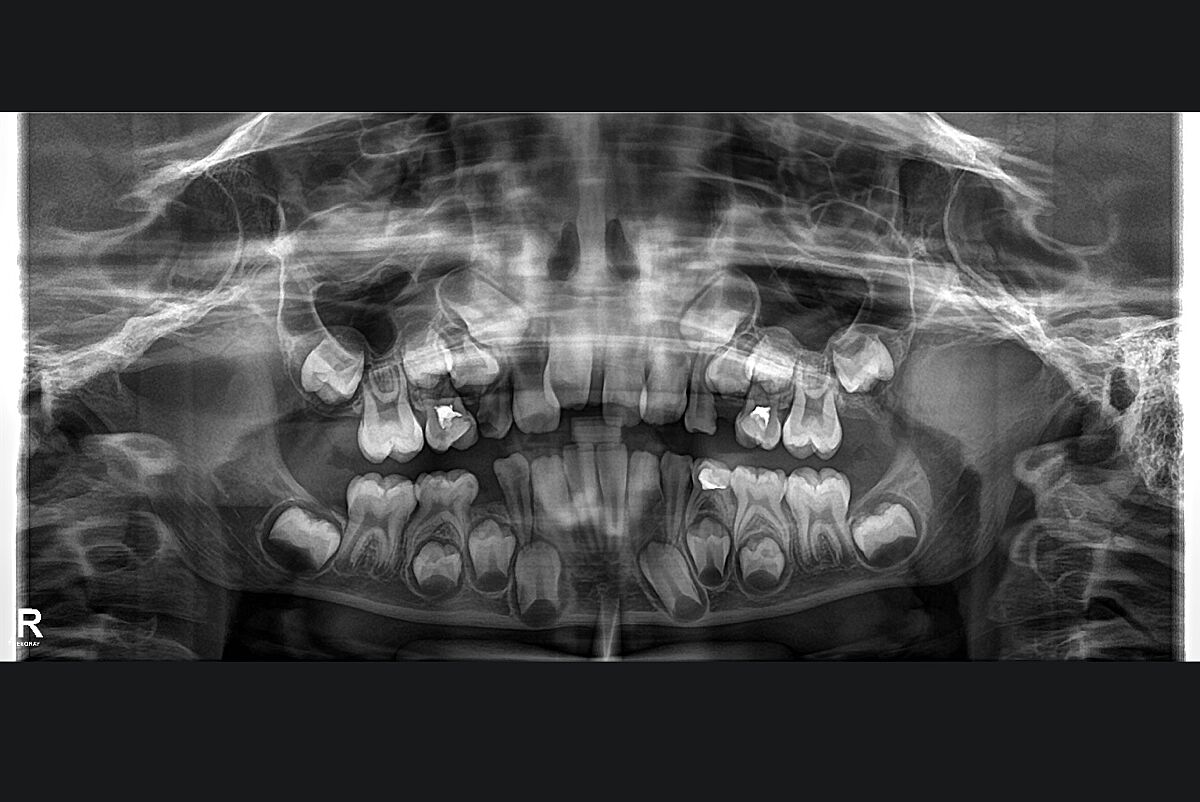

Девочки, возможно у кого то у детей было такое? Передние зубы поменялись местами( единицы и двойки) коренные. Что делать теперь не знаю, ортодонт тоже пока в замешательстве. Жду консультацию другого специалиста, интересно мнение со стороны

Нічого тут не мінялося місцями. Зверніться до більш кваліфікованих ортодонтів.

Скорее всего у вас узкая челюсть. Пока есть молочные моляры, вам нужно ставить аппарат Марко Роса для расширения челюсти, потом будет поздно. Ищите ортодонта, который умеет расширять челюсть на сменном прикусе несъемными аппаратами, а не скажет, чтобы приходили в 15 лет за брекетами

Это определяется как смена положения двух постоянных соседних зубов, расположенных в одном квадранте зубной дуги .

В процессе закладывания зубов они меняются местами еще в утробе как я поняла в нашем случае.

Изначально с вопросом расширения челюсти я и обратилась к ортодонту. Но тут он такие детали выявил по снимку

Нет! Об этом и речи не было. Посмотрите внимательно на форму Зубов, и их положение.